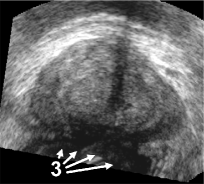

Figure 2: Fig. (a) shows a prostate volume with calcifications [1,2]. Fig. (b) shows a second volume after rigid registration; low probe pressure led to the low contrast zone [3]. Fig. (c) shows the 3D elastic registration with standard SSD; the whole prostate is dragged towards zone [3]. Fig. (d) shows the 3D intensity shift filtered, inverse consistent elastic registration; the strong intensity differences between both volumes are correctly handled, the calcifications make appearance at the correct position (best viewed in PDF with zoom).